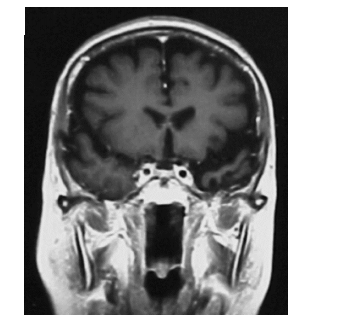

Observe abaixo a imagem por ressonância magnética

A imagem de um corte frontal mostra um paciente com demência semântica, em que se observa